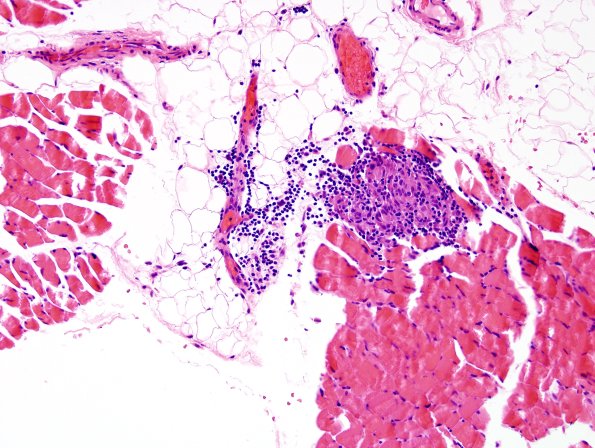

1B1 Sarcoid, no bugs (Case 1) Muscle 3

Sarcoid, in distinction to leprosy, do involve skeletal muscle (H&E)